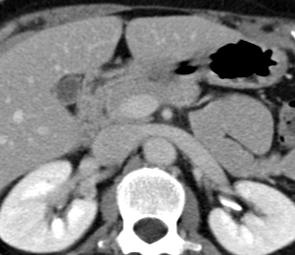

其他断层影像学包括计算机体层成像(CT)【11,12】或者磁共振成像(MRI),一般都用于排除其他疾病,例如肿瘤和子宫肌瘤。但Zafer Koc【11】等人报告324例无症状盆腔充血综合征通过多排CT决定是否左肾静脉变异和盆腔充血综合症的关系。研究显示左肾静脉变异可能是无症状盆腔静脉曲张的一个因素。

多排 CT 造影总量 90-120 cc 注射速率 3cc/s 动脉期采集图像 (45’’) : 肾静脉显示

左肾静脉回流异常(前胡桃夹子综合症-anterior Nutcracker Syndrome)

后胡桃夹子综合症 posterior Nutcracker Syndrome